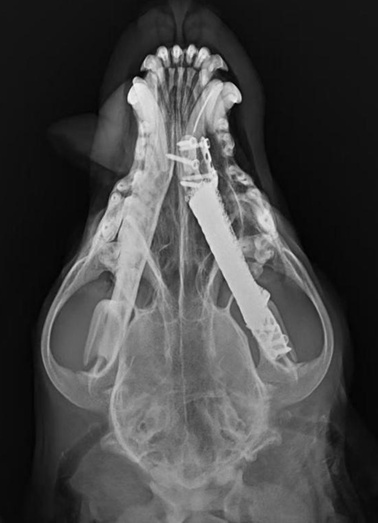

近日,闵行区柏萃动物医院成功实施了一例高难度手术:为一只下颌骨被肿瘤侵袭大半的柴犬,植入了量身定制的3D打印金属下颌骨。

这只8岁的柴犬,因口腔棘皮瘤困扰三年,期间反复经历口腔出血、疼痛、拔牙及肿瘤切除手术,生活质量极差。近期病情加剧,出现吞咽困难和大出血,影像学检查显示肿瘤已侵袭近半下颌骨。 面对这一复杂病例,闵行区柏萃动物医院由多学科团队(MDT)共同会诊,制定了周密的治疗方案:先行牙科预处理(部分牙齿根管治疗与拔除),再实施下颌骨部分切除,并同期植入为其量身定制的3D打印金属下颌骨。 手术取得圆满成功。术后,这只柴犬恢复了自主进食能力,流口水和口臭问题得到根本性改善,无须特殊护理,真正实现了生活质量的飞跃。

如今,随着3D打印技术在兽医临床的应用,我们有了更优的选择。在精准切除肿瘤后,我们可以利用3D打印技术,定制与原生骨骼形态高度契合的金属植入体,用以重建下颌结构。这种方式不仅能有效维持颌面的骨骼稳定性,更旨在让动物在术后恢复正常的口腔功能,从而真正提升其生活品质与生存时间。

手术切除是治疗下颌骨肿瘤的基础。然而,传统的切除手术意味着功能和外观的永久性丧失。3D打印重建技术的引入,标志着兽医外科从“治病保命”向“功能与生活质量并重”的理念进阶。它不仅能根除疾病,更能实现下颌骨的解剖学与功能学重建,极大地减轻了宠主的术后护理压力。